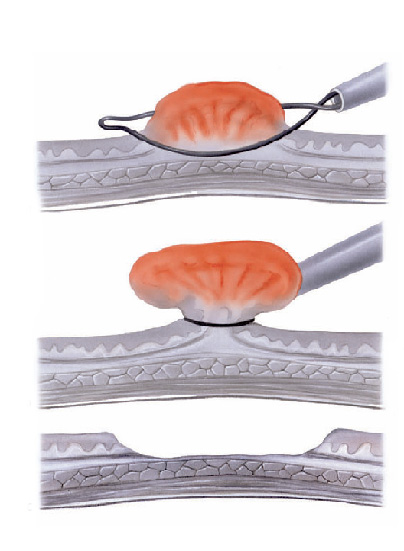

Polipectomia com alça diatérmica

Pólipos maiores necessitam ser removidos com alça e corrente de cauterização. Este procedimento permite cortar a base do pólipo e ao mesmo tempo coagular o local para evitar sangramentos.

Porém alguns pólipos possuem a base (pedículo) largo onde passam vasos calibrosos e por isto tem risco aumentado de sangramento na retirada mesmo usando a corrente de coagulação.

Nestes casos algumas medidas podem ser realizadas para diminuir o risco de sangramento:

Injeção de adrenalina na base do pólipo

Colocação de um laço na base do pólipo para estrangular o pedículo

Alguns pólipos são tão grandes que não podem ser removidos inteiros. Nestes casos o pólipo é retirado em pedaços para poder garantir a sua remoção completa.

Alguns pólipos não possuem a base alongada (pedículo), estes são chamados de pólipos sésseis. A remoção destes pólipos possui risco maior de perfuração do órgão pois como são planos ficam muito próximos da parede externa do órgão.

Mucosectomia

Para diminuir este risco, injeta-se com um uma agulha uma solução abaixo do pólipo para que ele levante e fique mais longe da parede do órgão. Após isto passa-se a alça diatérmica e realiza-se o

procedimento de polipectomia.